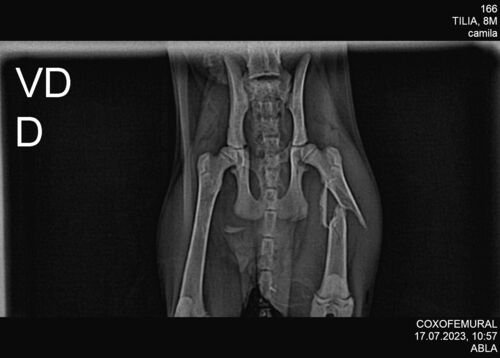

A Otilia é uma gatinha de quase quatro meses que em um dia chegou em casa com a perna com problema. Foi feito exames que constatou a fratura, desde então emagreceu e precisa de ser aliviada rapidamente. Nossa família está juntando para tentar ajudar nos procedimentos que ficarão em torno de R$ 3.140,00. Se vo ê sentir do coração que pode ajudar, qualquer quantia, será muito bem vinda. Desde já agradecemos ♥️🐱